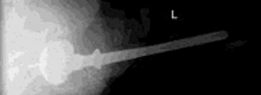

- الأشعة السينية (Radiographs): تُعد أشعة الحوض الأمامية الخلفية القياسية، وأشعة الورك الجانبية الحقيقية، وأشعة الفخذ بالطول الكامل ضرورية. تُوفر هذه الأشعة تقييمًا أساسيًا لوضع الغرسة وسلامتها وتقييمًا أوليًا لعيوب العظم. يُمكن أن تُساعد الأشعة المقارنة للورك المقابل في تحديد الأبعاد وفهم اختلاف طول الساق.

التصوير المقطعي المحوسب (CT Scan):

يُعد التصوير المقطعي المحوسب بتقنية تقليل تشوه المعدن (MARS) لا يُقدر بثمن. يُوفر معلومات مفصلة ثلاثية الأبعاد حول مدى وشكل عيوب العظم، مما يُساعد في التصنيف الدقيق لعيوب بابروسكي لكل من مفصل الحوض وعظم الفخذ. يُساعد في تحديد العيوب التجويفية مقابل العيوب القطعية، وتقييم سلامة الأعمدة، وتحديد مناطق النوافذ القشرية أو ترقق القشرة. تُوجه هذه المعلومات اختيار دعامات أو أقماع أو أكمام المعدن عالي المسامية المحددة. يُمكن للأستاذ الدكتور محمد هطيف استخدام هذه الصور لتحديد أفضل خطة جراحية.